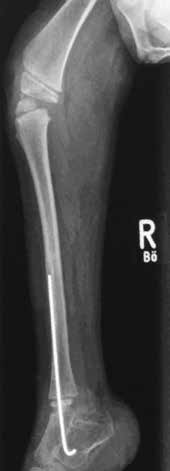

Anamnese und Diagnose (Abb. 7a–c)

In der Woche vor dem Geburtstermin kommt im Rahmen einer sonographischen Untersuchung des Patienten der Verdacht auf ein Steißbeinteratom der Mutter mit Differentialdiagnose Plazentatumor (Rhabdomyosarkom) auf. Perinatal erweist sich dies jedoch als Weichteilsarkom des Unterschenkels des Patienten. In der Folge wird der Patient an seinem zweiten Lebenstag linksseitig transtibial amputiert (Abb. 7c). Im weiteren Verlauf erhält er teilstationär Chemotherapie.